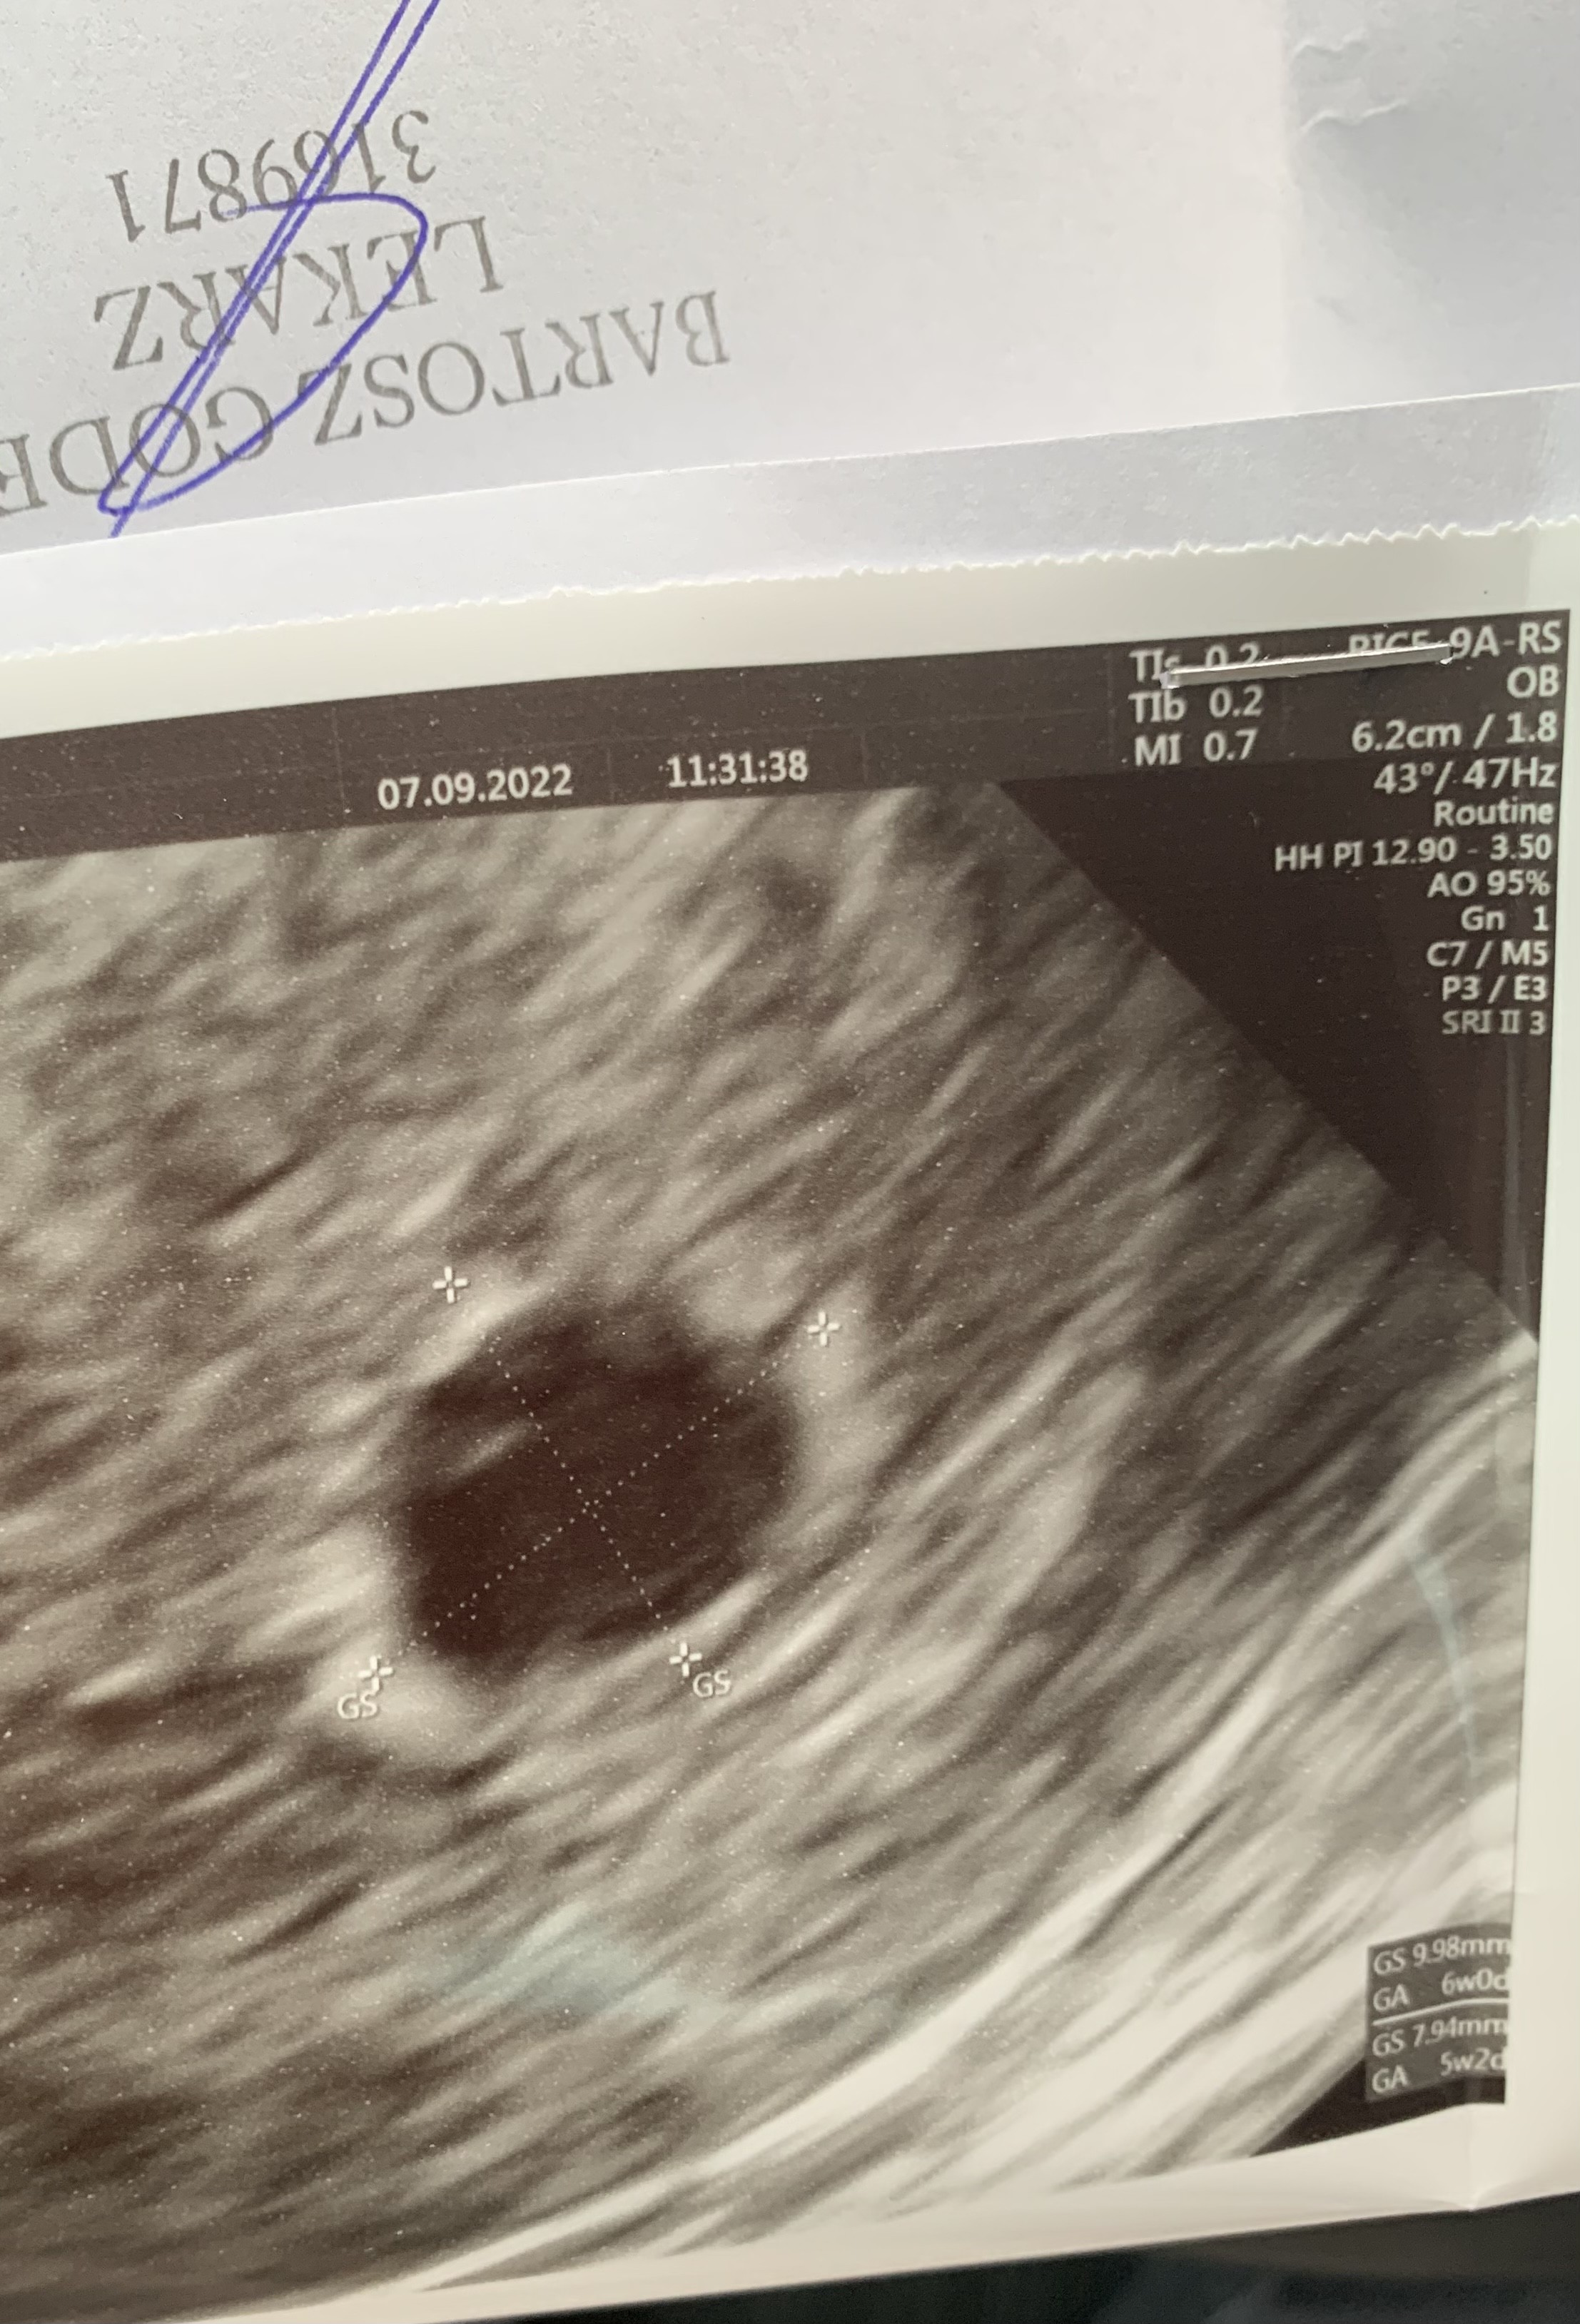

To są zdjęcia z tego USG 7 września? Jeśli lekarz nie widzi pęcherzyka żółtkowego to raczej my też go tam nie zobaczymy.Dziewczyny 7 wrześni byłam na pierwszym usg. W macicy widoczny pęcherzyk ciążowy o wym 9,98 x 7.94. Brak pęcherzyka żółtkowego. Następne usg 19 września. Ostatnia miesiączka 25 lipca. Przeważnie cykle 31-33 dni. Myślicie, że jest szansa że pijawi się jeszcze pęcgerzyk żółtkowy i zarodek. Na usg widać w pęcherzyku jakąś dziwna smuge. Beta w dniu usg ponad 4600

Ciężko stwierdzić , za wczesnienwtedy było na usg.Dziewczyny 7 wrześni byłam na pierwszym usg. W macicy widoczny pęcherzyk ciążowy o wym 9,98 x 7.94. Brak pęcherzyka żółtkowego. Następne usg 19 września. Ostatnia miesiączka 25 lipca. Przeważnie cykle 31-33 dni. Myślicie, że jest szansa że pijawi się jeszcze pęcgerzyk żółtkowy i zarodek. Na usg widać w pęcherzyku jakąś dziwna smuge. Beta w dniu usg ponad 4600